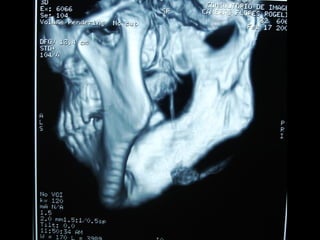

Angiografía carotídea

Quiste piso de boca

Quiste glóbulomaxilar

Quiste seno maxilar

Quiste mandibular